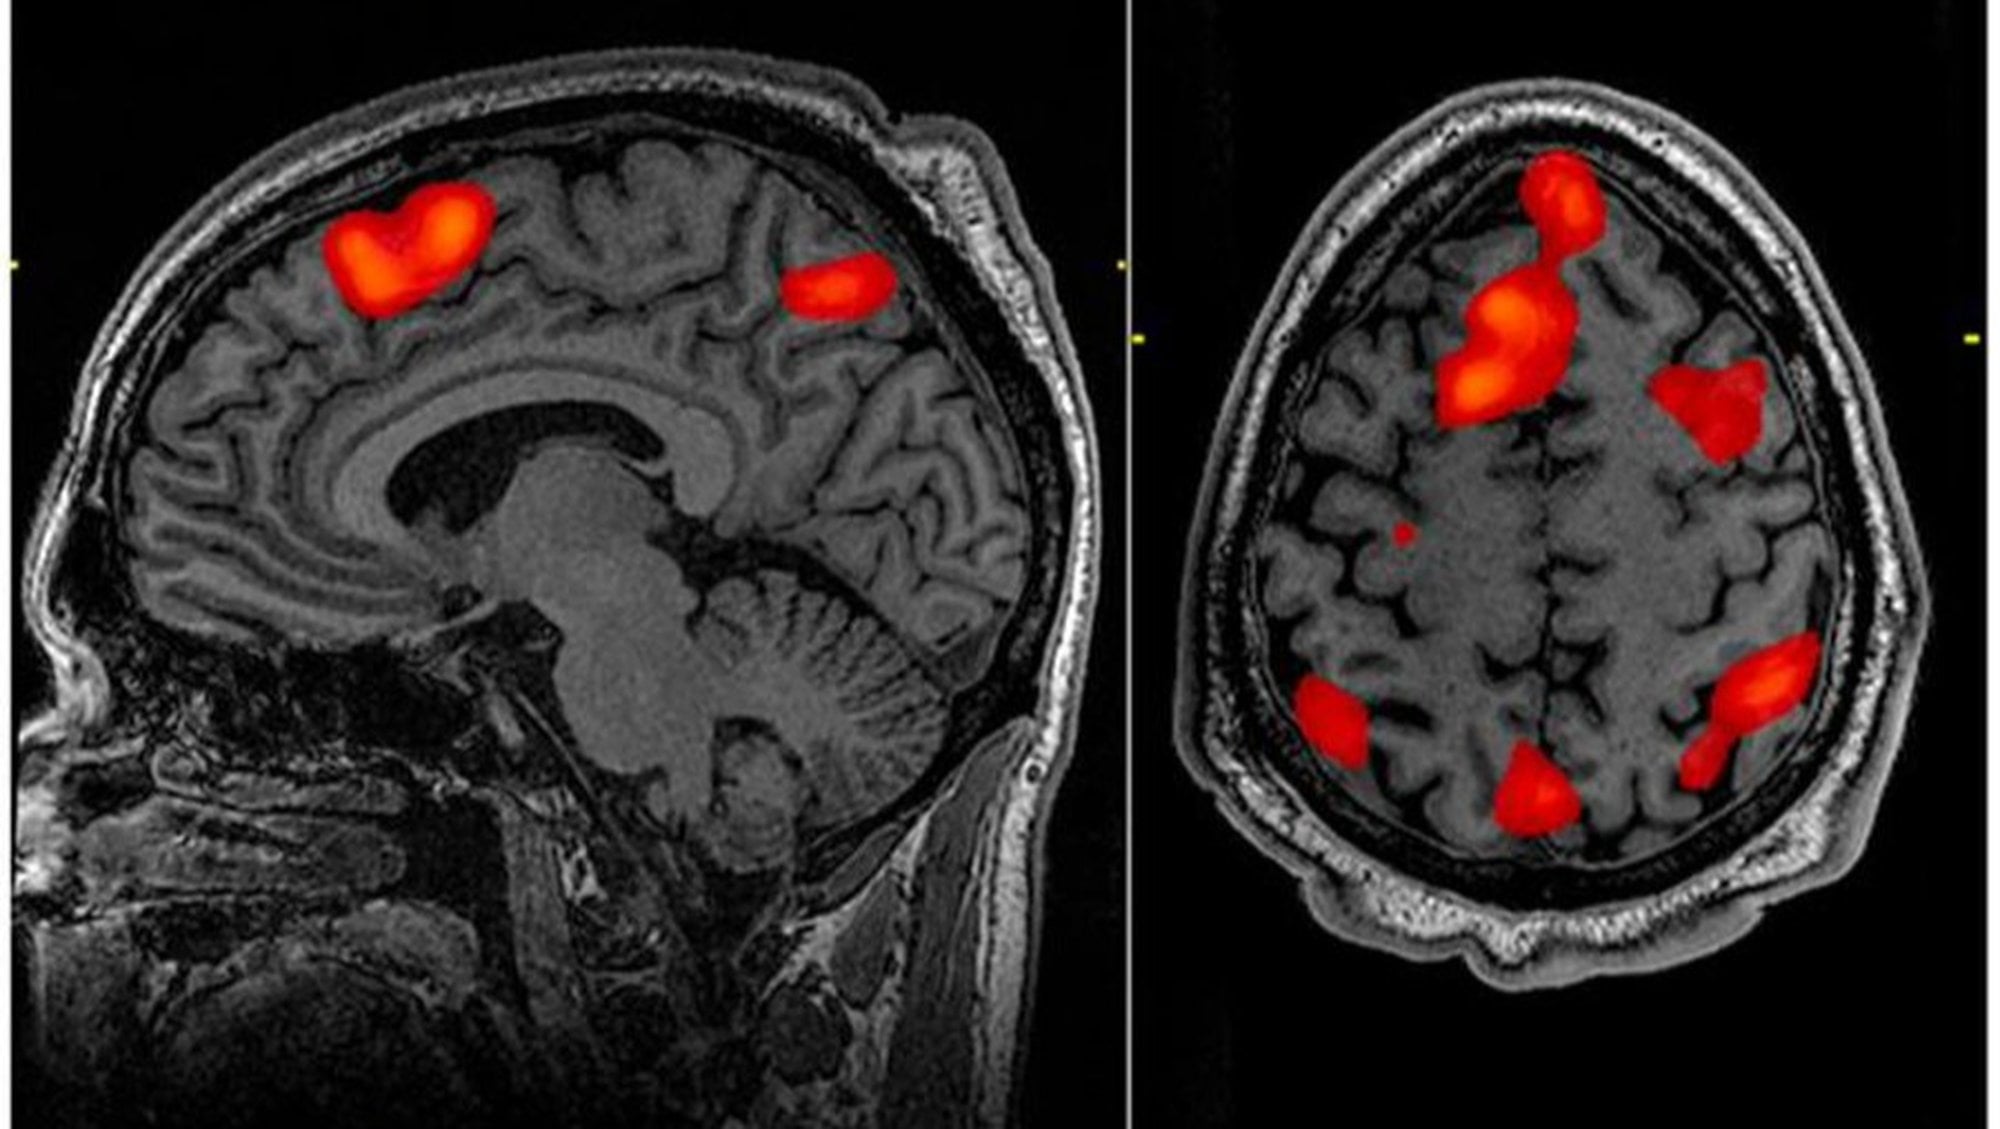

Kanada'da bilim insanları,epilepsi tedavisi gören 87 yaşındaki bir hastanın elektroensefalografi (EEG) ile beyin aktiviteleri incelenirken hasta aniden kalp krizi geçirdi.Elektroensefalografiye bağlı olan hastanın hayatını kaybederken son beyin aktiviteleri de 15 dakika boyunca kayıt altına alındı.

Sonucunda rüya görme, geçmişi hatırlama gibi işlevlerin yapıldıgını buldular bunuda "Frontiers in the Neuroscience of Aging"dergisinde yayınladılar.